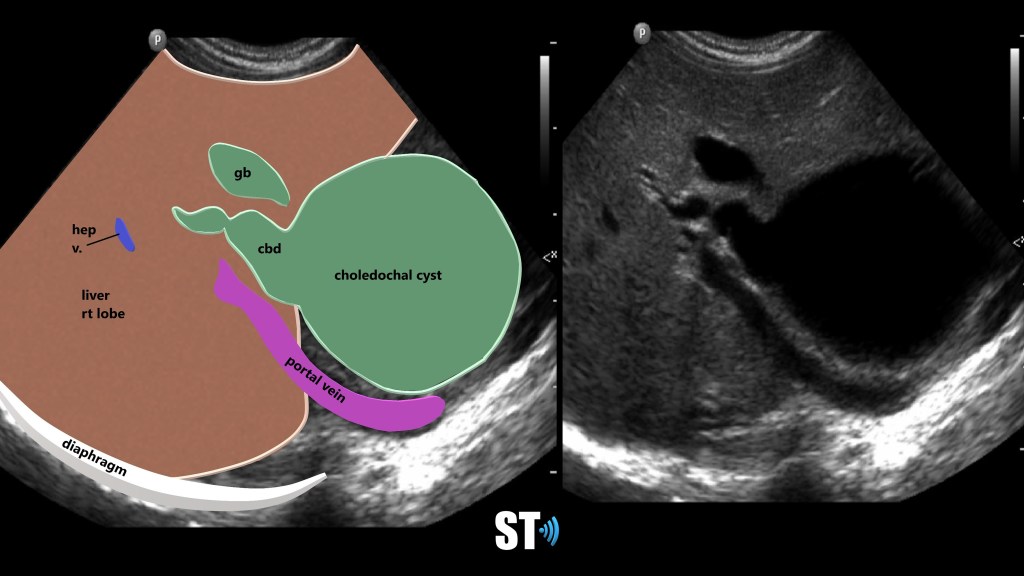

Choledochal cysts are routinely found on ultrasound in infancy, though they can be found on adults and fetal scans as shown below. An anechoic cyst will be present at or before the porta hepatis, size may be variable from small to quite large. In Caroli disease there will be innumerable intrahepatic cysts, this my be difficult to differentiate from polycystic kidney disease (ADPCKD) affecting the liver, typically ADPCKD cysts are non communicating. [3] Once found further imaging and work up must take place to properly classify and treat CC. Endoscopic Retrograde CholanigoPancreatography (ERCP) is the gold standard in diagnosing CC, however Magnetic Resonance CholangioPancreatography (MRCP) is now favored over ERCP due to its non-invasiveness and superior resolution. [5]